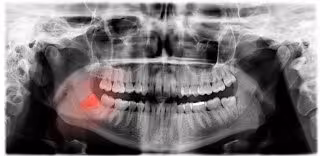

Este motivo también explica el hecho de que muchas personas ni siquiera desarrollen "el germen dentario de los terceros molares y nunca los tendrán". Esta circunstancia, no obstante, ha de diferenciarse del hecho de que los terceros molares no puedan salir aun formados. "En muchos casos, la radiografía revela la presencia de esos molares, incluidos en el hueso y sin posibilidad de salir por falta de espacio", especifica el doctor Castro.

De hecho, es la falta de espacio la fuente de los problemas que pueden ocasionar los terceros molares. Entre los más frecuentes, el experto cita los quistes alrededor de la muela del juicio y la pericoronaritis o inflamación de la encía alrededor de la muela del juicio. Finalmente, también entre los más comunes, "una incorrecta posición inclinada del tercer molar puede dañar al diente contiguo. Bien reabsorbiendo su raíz, bien empujándole y ocasionando variaciones en la arcada dentaria", informa el experto.